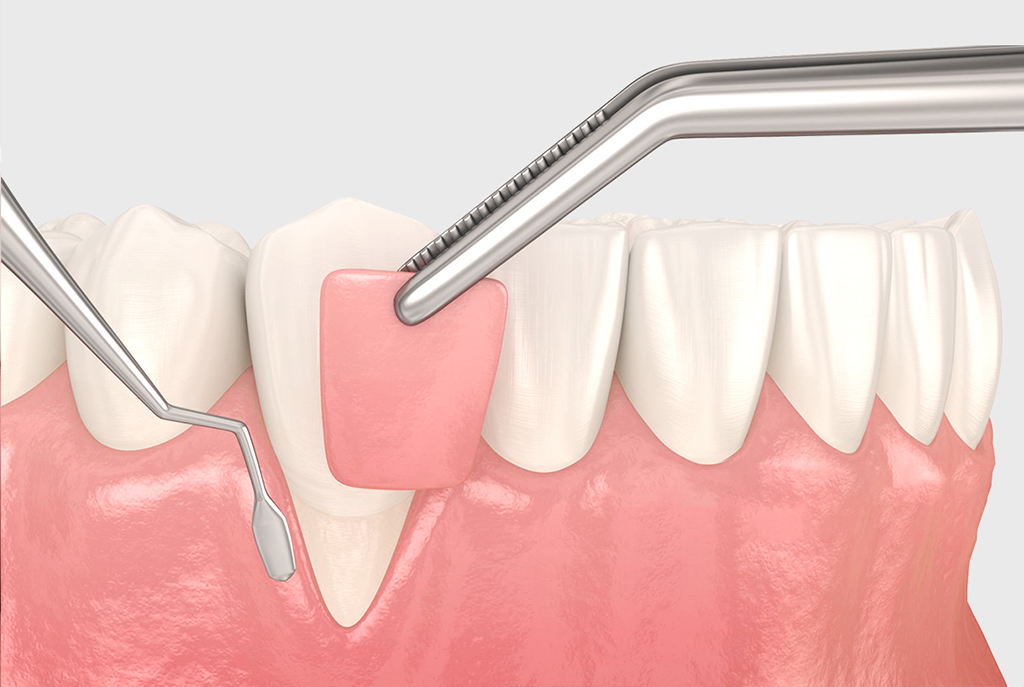

會先上麻醉,過程不會痛。將牙齦切開與翻開後,清除所有發炎組織、牙結石,確認牙根與骨頭表面乾淨無虞,再進行骨粉等生醫材料的放置,最後進行傷口的縫合。

局部麻醉、切開翻瓣、牙周清創

補骨

縫合